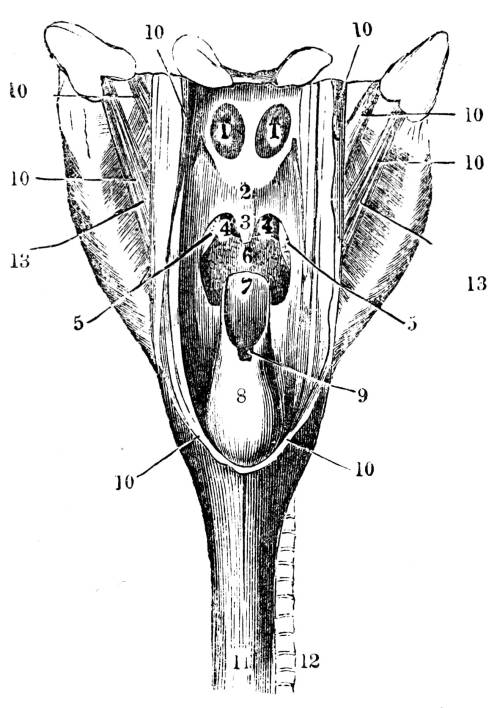

Fig. CXXXVI.—

Posterior View of the Larynx and

Trachea.

1. The os hyoides. 2. Thyroid cartilage. 3. Cricoid

cartilage. 4. Arytenoid cartilages, separated from each other.

5. Epiglottis. 6. Opening of the glottis. 7. Termination of the

cartilaginous rings of the trachea. 8. The ligamentous portion of the

trachea. 9. Trachea laid open, showing its internal mucous surface

and follicles, with the anterior portion of the cartilaginous rings

appearing through it.

362. The first portion of the windpipe called

the larynx (figs. CXXXV. and CXXXVI. ), constitutes

the organ of the voice. It is situated at the upper

and fore part of the neck (fig. CLIII. 7, 9), immediately

under the bone to which the root of the40

tongue, called the os hyoides (figs. CLIII. 6, and

CXXXVI. 1), is attached. The larynx forms a

very complex structure, and is composed of a41

variety of cartilages, muscles, ligaments, membranes,

and mucous glands (fig. CXXXVI. 2, 3, 4,

5). At its upper part is a narrow opening of a

triangular figure called the glottis (fig. CXXXVI.

6), by which air is admitted to and from the lung.

Immediately above this opening is placed the

cartilage, which obtains its name from its situation,

epiglottis (fig. CXXXVI. 5), which is attached to

the root of the tongue (fig. CLIII. 6, 7), and which

may be distinctly seen in the living body by pressing

down the tongue.

363. The Epiglottis is highly elastic, and is an

agent of no inconsiderable importance in respiration,

deglutition, and speaking. In respiration it

breaks the current of air which rushes to the lungs

through the mouth and nostrils, and prevents it

from flowing to the delicate air cells with too great

a degree of force. During the action of deglutition

the epiglottis is carried completely over the

glottis (fig. CLIII. 6, 7, 8), partly because it is

necessarily forced backwards, when the tongue

passes backwards in delivering the food to the

pharynx (fig. CLIII. 6, 7, 8, 10), partly because it is

carried backwards by certain minute muscles which

act directly upon it, and perhaps also partly in

consequence of its own peculiar irritability. The

moment the action of deglutition has been performed

the epiglottis springs from the aperture of

the glottis, partly by its own elasticity, and partly

by the return of the tongue to its former position.42

During the act of speaking the column of air which

is expelled from the lung, which rushes through

the glottis, and which thus forms the voice, strikes

against the epiglottis, and the voice becomes thereby

in some degree modified.

View of the trachea, showing, first, the division of the

tube into the right and left bronchus, and the subdivision

of the bronchi into the bronchial tubes; and secondly, the

membranous and cartilaginous tissues of which the organ

is composed.